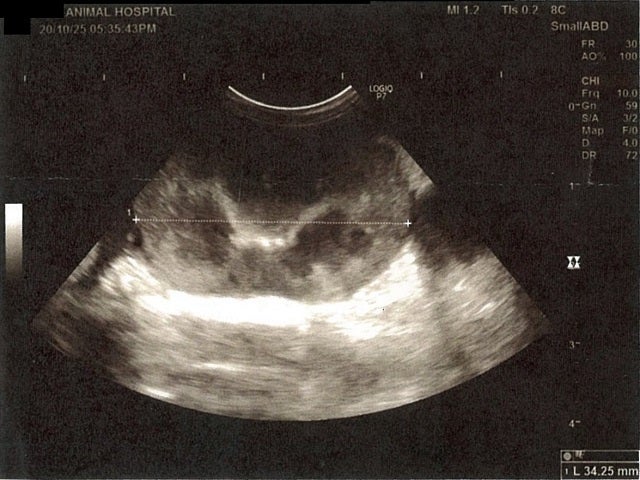

《心臓周りの胸部以外の全ての腹部で腹水がみられるとの診断です》

大網という部分で内臓を包む膜のようなものです。その周りに腹水が溜まっています。

右腎臓周りに腹水が確認できるエコー写真